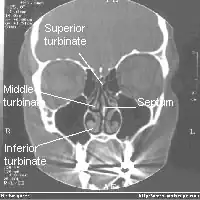

![]() Tomografía axial computarizada frontal del cráneo mostrando los senos paranasales. | ||

En anatomía, los senos nasales o paranasales son un conjunto de cavidades aéreas que se encuentran en los huesos frontales, esfenoides, etmoides, temporal y maxilar superior, que comunican con las fosas nasales. Estas cavidades son estructuras que influyen en la respiración, la fonación, el calentamiento y la olfacción adecuados.

Existen 8 senos paranasales, 4 a cada lado de la nariz y están cubiertos por epitelio respiratorio con moco (epitelio pseudoestratificado cilíndrico ciliado con células caliciformes).